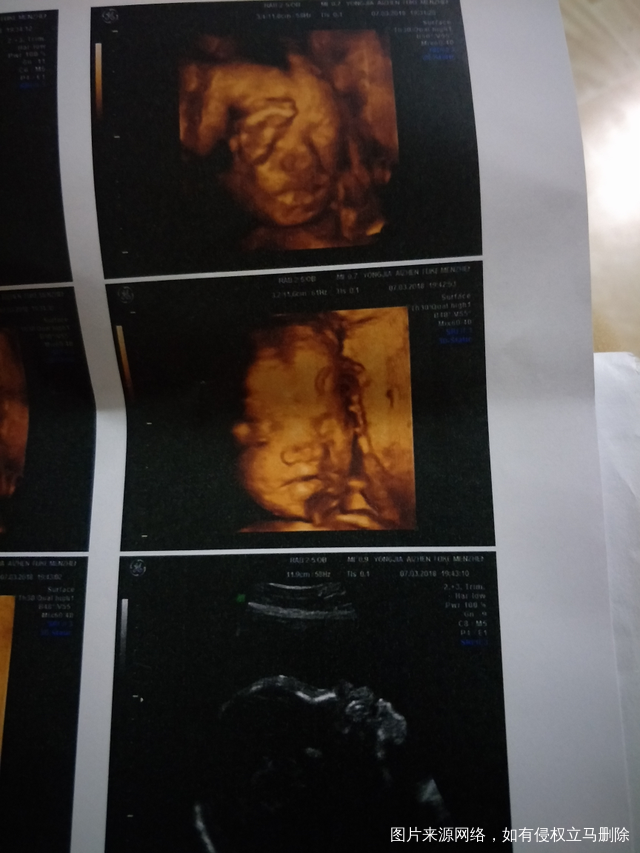

宝宝今天做四维b超一次通过,挺乖的,姐妹们看像男宝宝还是女宝宝呢?